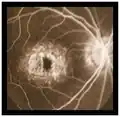

Fluoresceinografía digital

- Angiografía con fluoresceina: muestra una coroides oscura debido a depósitos de lipofuscina dentro del epitelio pigmentario de la retina e hiperfluorescencia macular debido al efecto ventana.